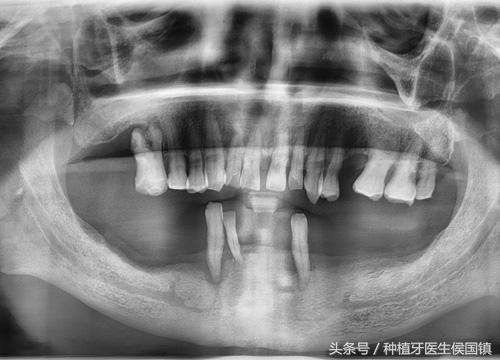

The second step is the initial diagnosis, the doctor communicates with the patient, understands the patient's situation and repair requirements, and clarifies the planting plan. The process requires a detailed examination, including blood pressure measurement, blood routine examination, dental film examination and so on.

dental film